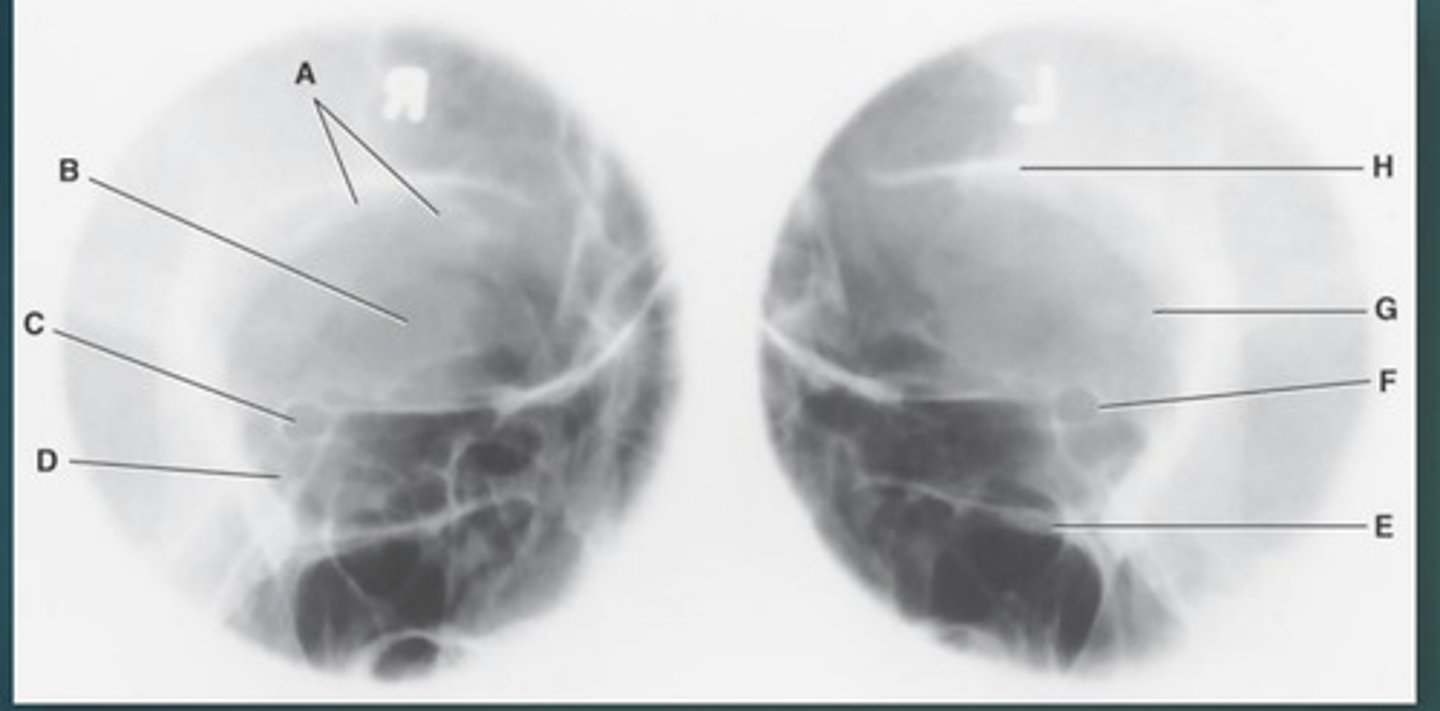

Lateral sinus

What position?

L. Orbital roofs

A.

L. Greater wings of sphenoid

B.

sella turcica of sphenoid

C.

L. Sphenoid sinus

D.

L. Rami of mandible

E.

L. Maxillary sinuses

F.

L. Ethmoid sinuses

G.

L. Frontal sinuses of frontal bone

H.